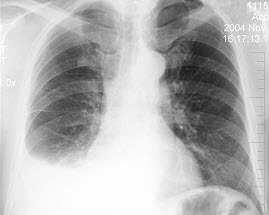

E.关节造影

男,35岁,发热、贫血、血尿,有副鼻窦炎,结合X线图像,最可能的诊断是()

E.韦格肉芽肿